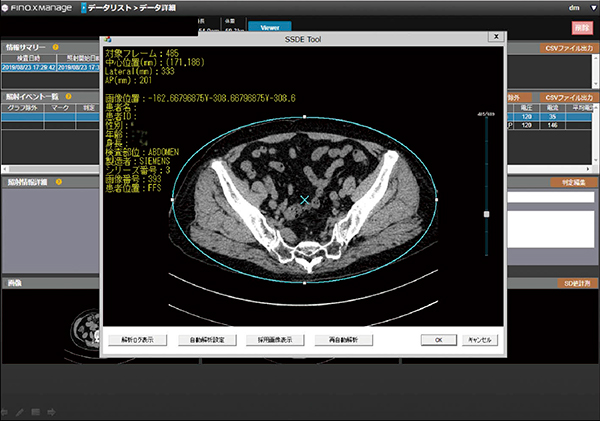

システム構成は,被ばく線量管理システムFINO.XManage,DICOM画像検像システム「NEOVISTA I-PACS QA」(共にコニカミノルタ社)で構成され,一般撮影マネージメント機能“RADInsight”は,FINO.XManageに実装されている(図2)。これにより,被ばく線量管理システムとDICOM画像検像システムをリンクさせることで,異常値が出た場合の画像・撮影部位・撮影長などの確認や,CT画像におけるDICOM画像を利用したSD計測,SSDEの自動算出(図3)機能などを,システム上で行える利点がある。

図3 SSDE自動算出画面